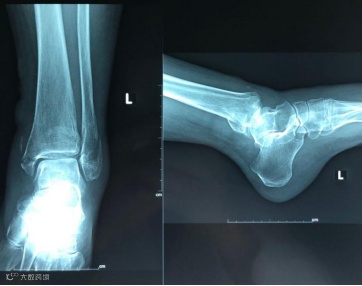

无独有偶,10月12日,一位72岁的老奶奶不慎扭伤了左踝,来到河南电力医院就诊。外二科值班医生迅速对患者进行查体,当时老奶奶的左小腿出现大面积淤血青紫斑,左足背、左踝关节肿胀压痛,活动障碍。

X线片提示,老奶奶左踝关节骨折,这种骨折也称Pilon氏骨折,属于关节内骨折,因关节常处于过伸状态,对复位要求十分严格,按骨科医生的说法是“最具挑战的骨折手术之一”。